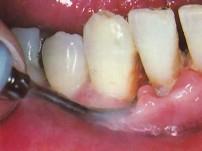

问题 使用超声波洁牙机时,工作头应与牙面成 ( )

选项 A.20度角左右 B.10度角左右 C.80度角左右 D.25度角左右 E.15度角左右

答案 E